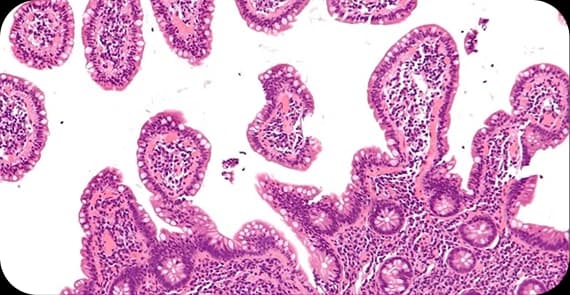

Lymph node biopsy

Lymphoma cancer diagnosis involves clinical evaluation and tissue confirmation.

The diagnostic process may include: